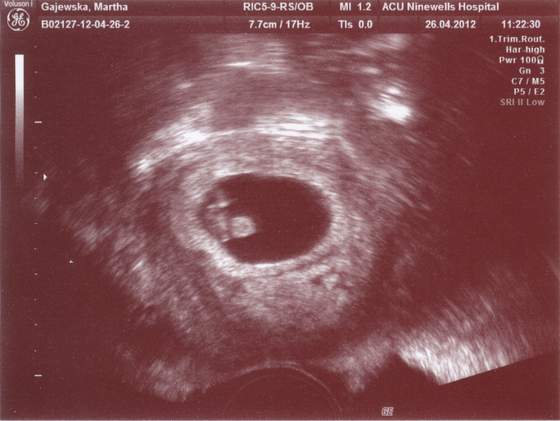

sliczne dzieciaczki ci rosna moje gratulacje.A tutaj obiecane fotki ze scanu

Bliźniak pierwszy 9 mm

Zobacz załącznik 459763